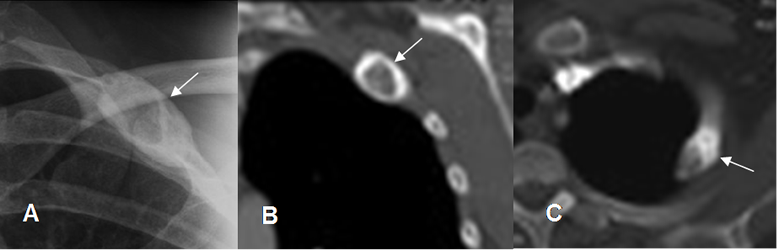

Fig 102 A. Displasia fibrosa.

A: Rx AP, B: TAC reconstrucción coronal y C: TAC axial. Lesión expansiva de bordes escleróticos en el arco anterior de la 2º costilla, por displasia fibrosa.